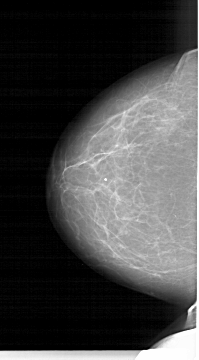

A_1264_1.LEFT_CC

LEFT_CC LINES 6106 PIXELS_PER_LINE 3376 BITS_PER_PIXEL 12 RESOLUTION 43.5 NON_OVERLAY